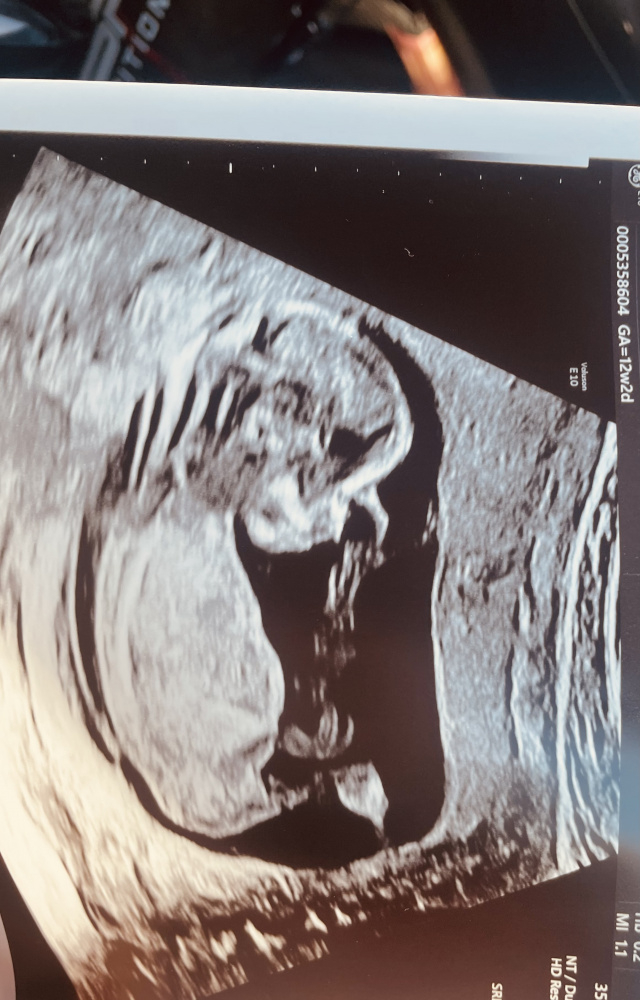

natürlich ist uns in erster Linie wichtig, dass unser Kind gesund ist. Dem scheint glücklicherweise so zu sein. Die Pränataldiagnostikerin meinte ein Geschlecht erkannt zu haben, nannte jedoch aus rechtlichen Gründen nicht welches sie meint. Könnt ihr anhand der Fotos ein Geschlecht erkennen?